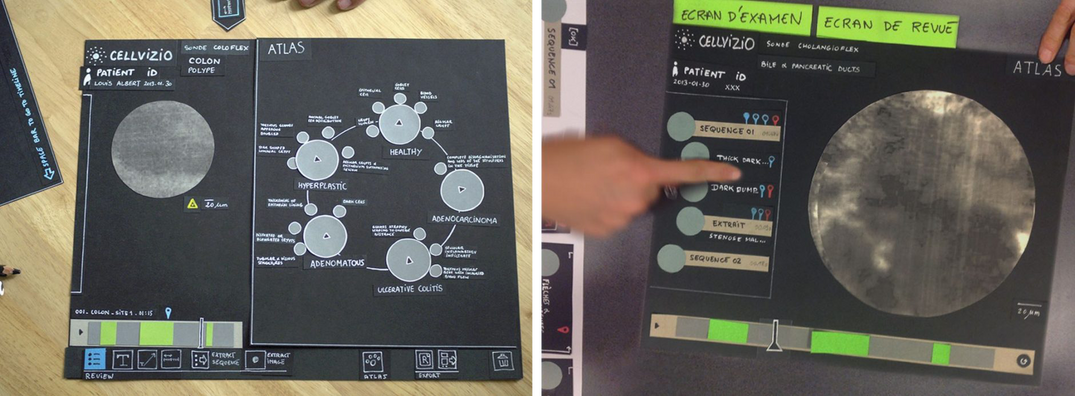

Des observations d’usage en milieu clinique suivies de séances de conception ont permis d’imaginer de nouvelles interactions et fonctionnalités.

L’enjeu principal du design a été de concilier sur un même écran la visualisation des séquences transmises par la sonde avec les nouveaux outils conçus pour accompagner le gastroentérologue dans sa procédure médicale.

• Faciliter la lecture et la compréhension de l’imagerie microscopique grâce à une base de données de référence composée d’images et de vidéos (atlas) ;